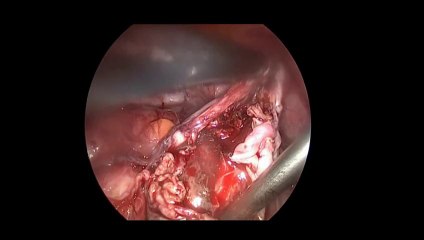

Diagnostik laparoskopi - Prof. Dr. Aydan Biri